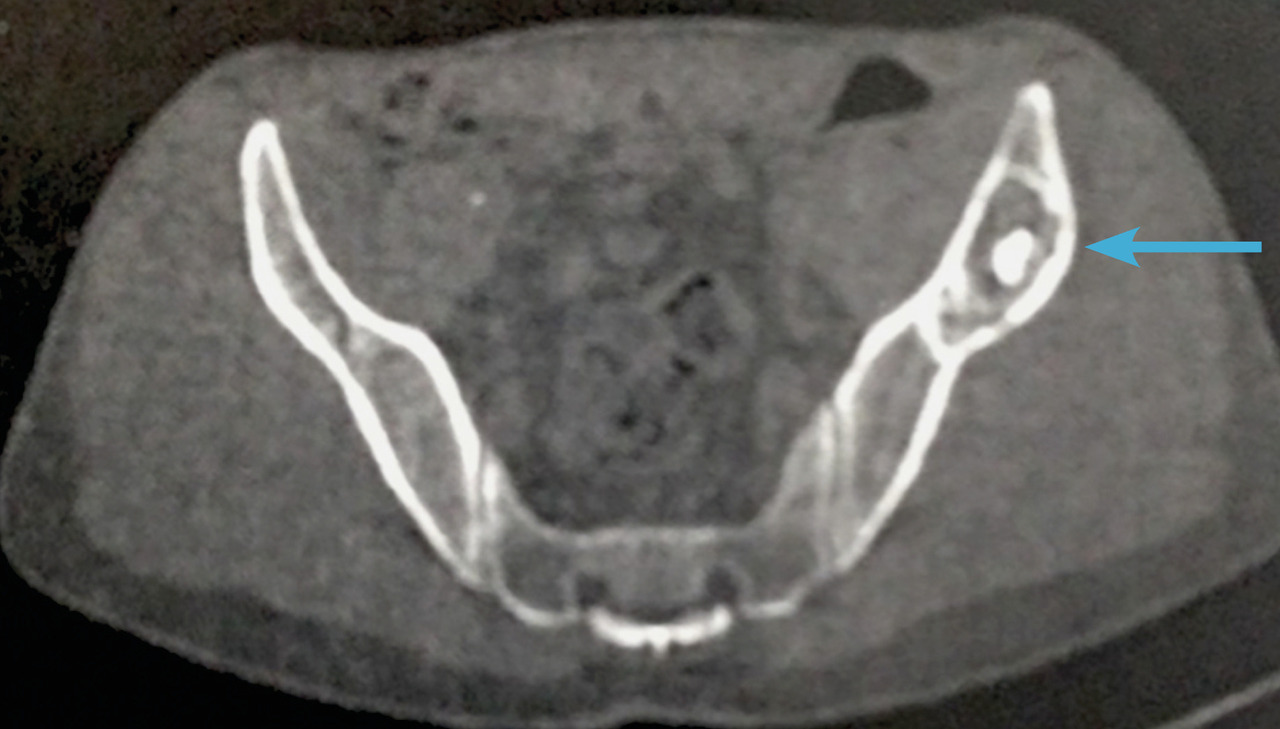

Un complément d’imagerie par TDM (fig. 2 ) confirme l’existence d’une lésion soufflante mixte (graisse et os) non vascularisée à caractère très probablement bénin, évoquant soit un kyste osseux solitaire vieilli, soit une dysplasie fibreuse, de localisation tout à fait singulière.

Un complément d’imagerie par TDM (